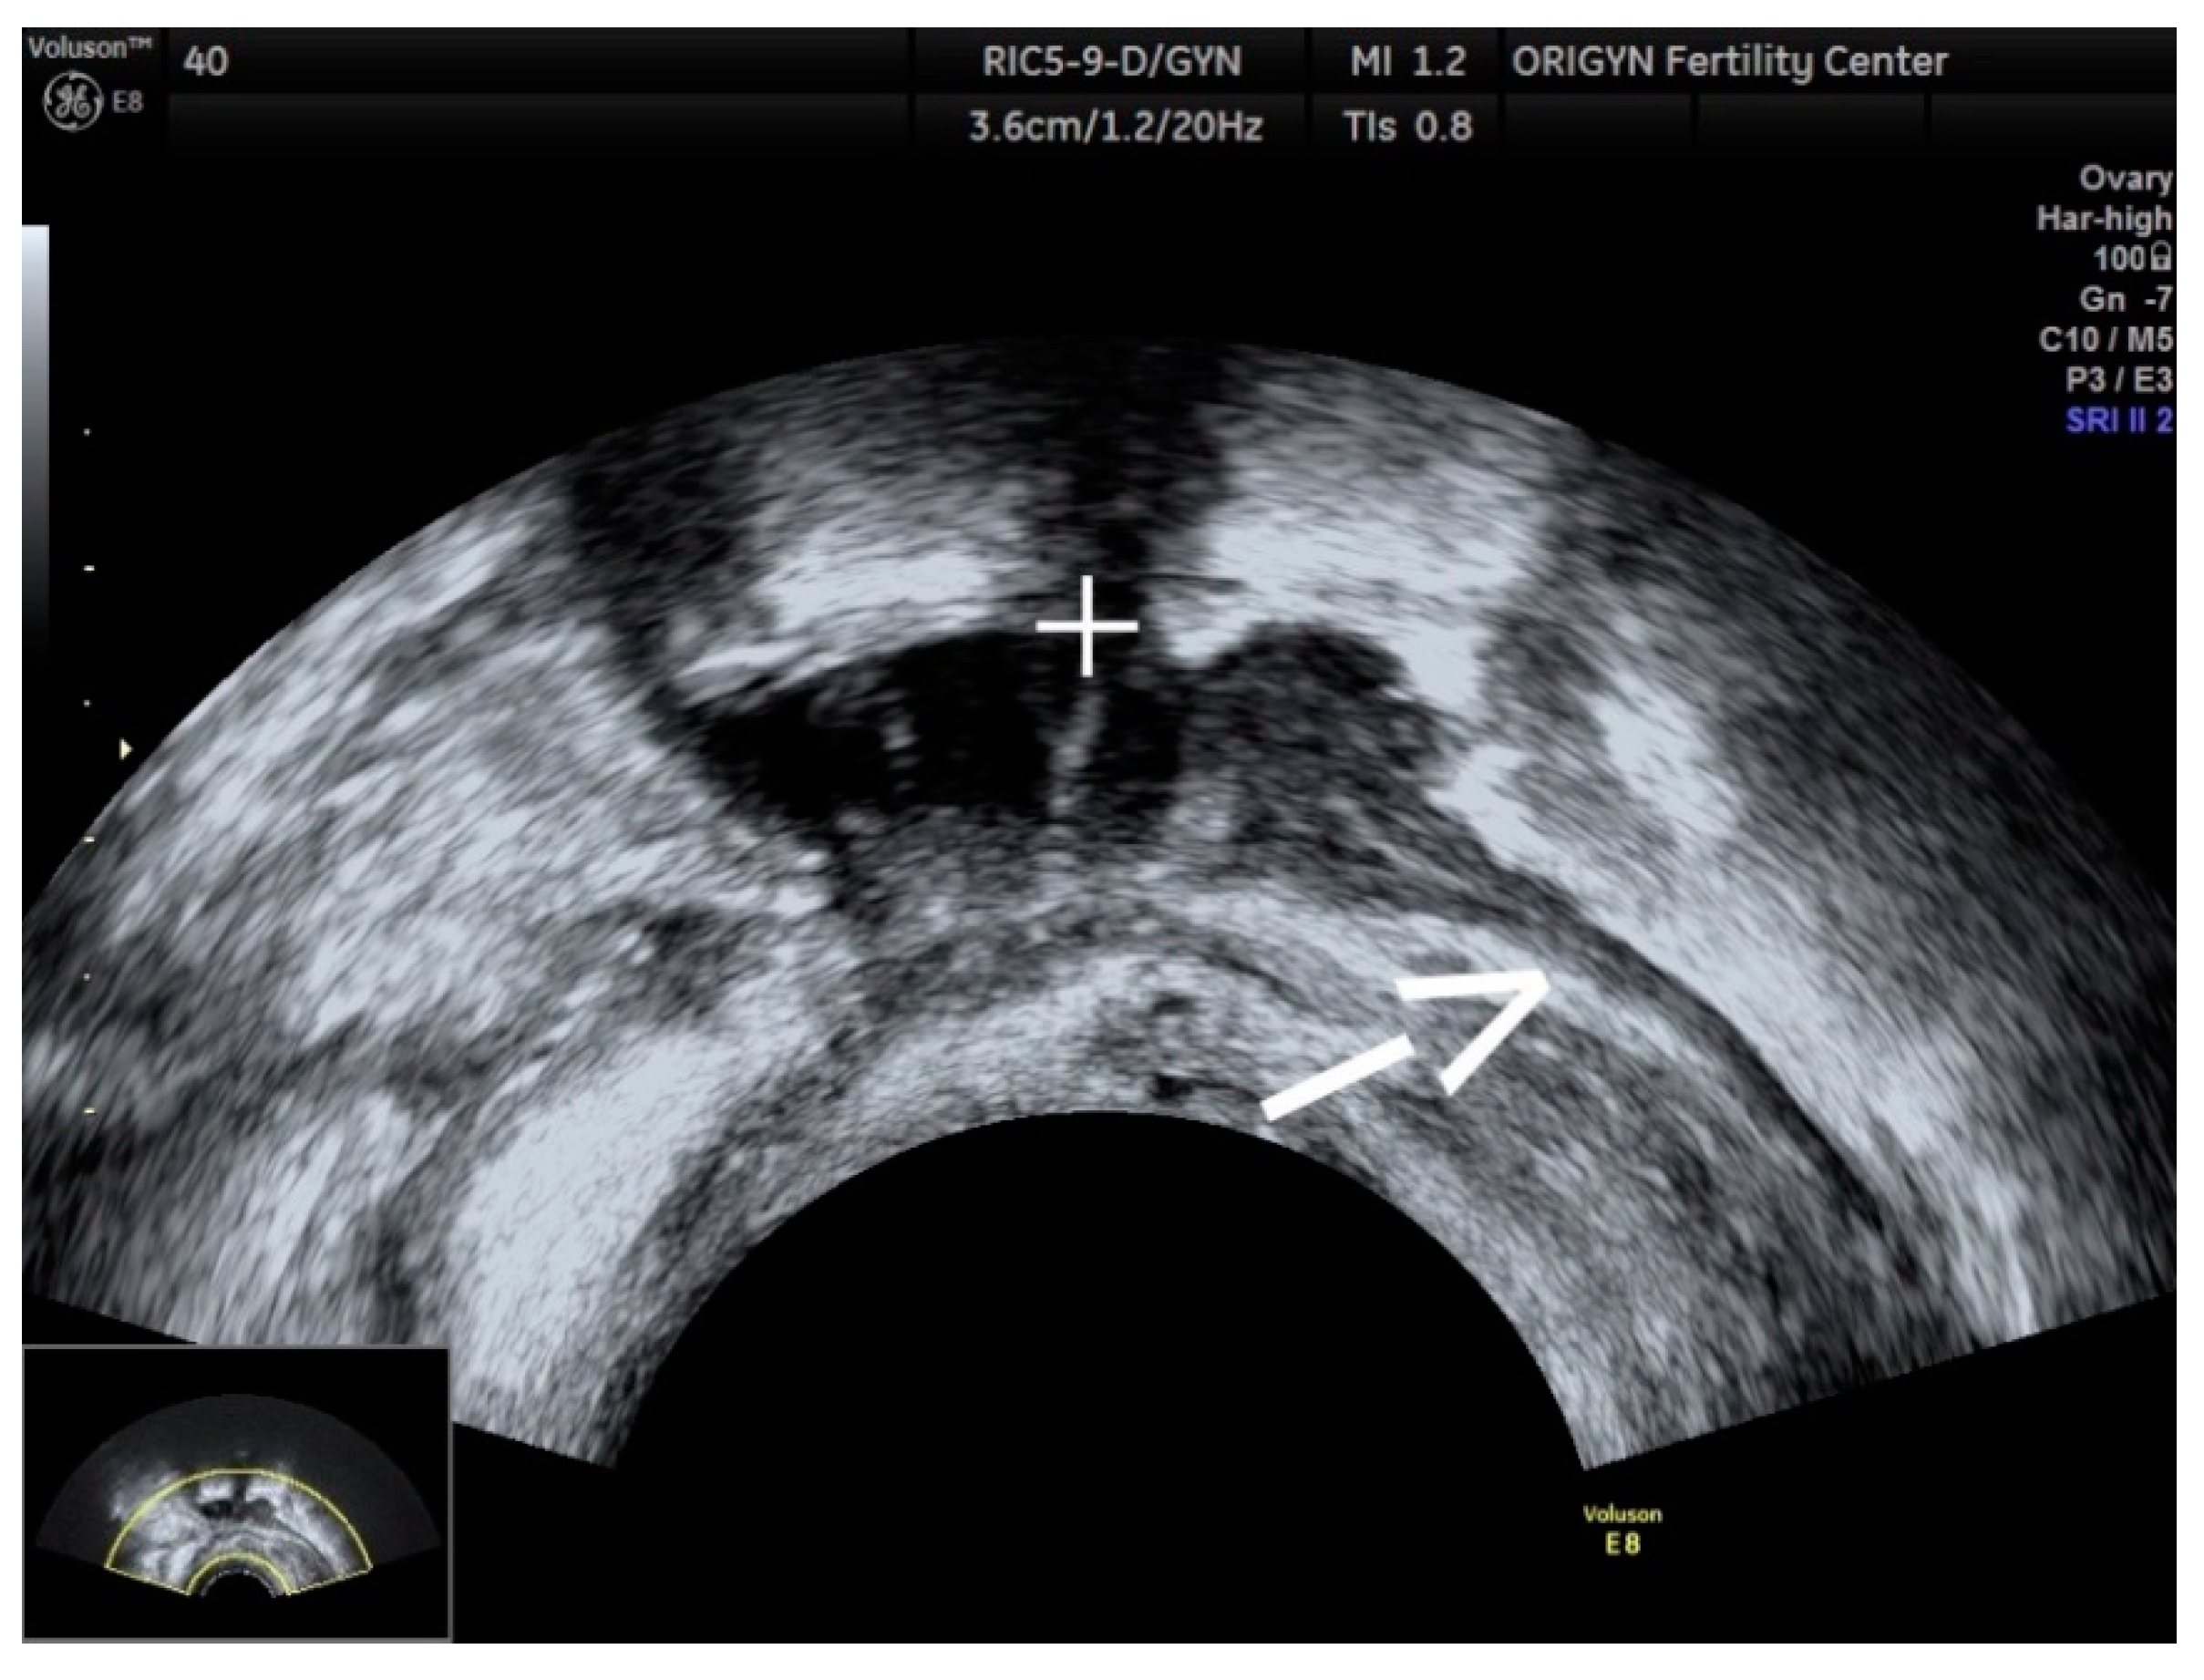

3.1. ADNEXA